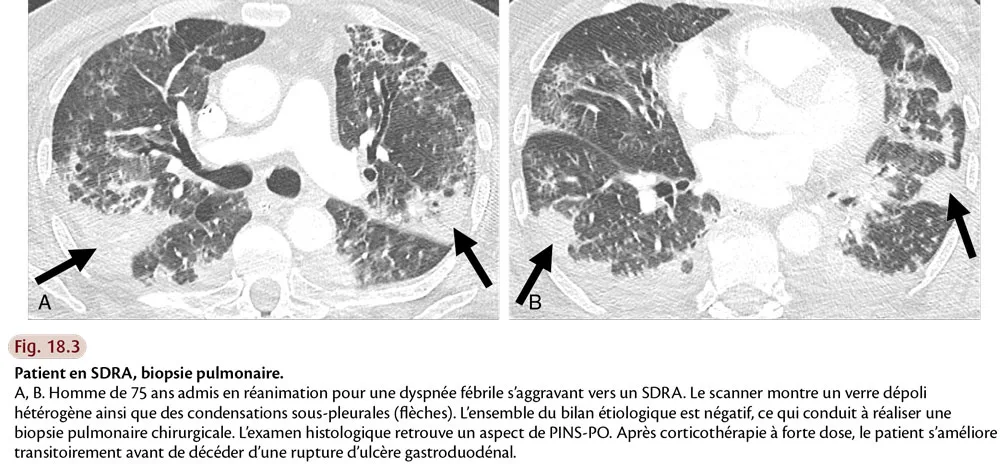

Devant un poumon de réanimation, le radiologue doit, dans la mesure du possible, essayer d’identifier un pattern TDM, et rechercher en particulier un aspect de PIA, mais aussi d’éventuels diagnostics différentiels (fig. 18.3). Il doit également traquer les comorbidités : pneumothorax, pneumomédiastin, emphysème sous-cutané, embolie pulmonaire, mauvais positionnement des cathéters, drains ou sondes (fig. 18.4).

Fig.18.3